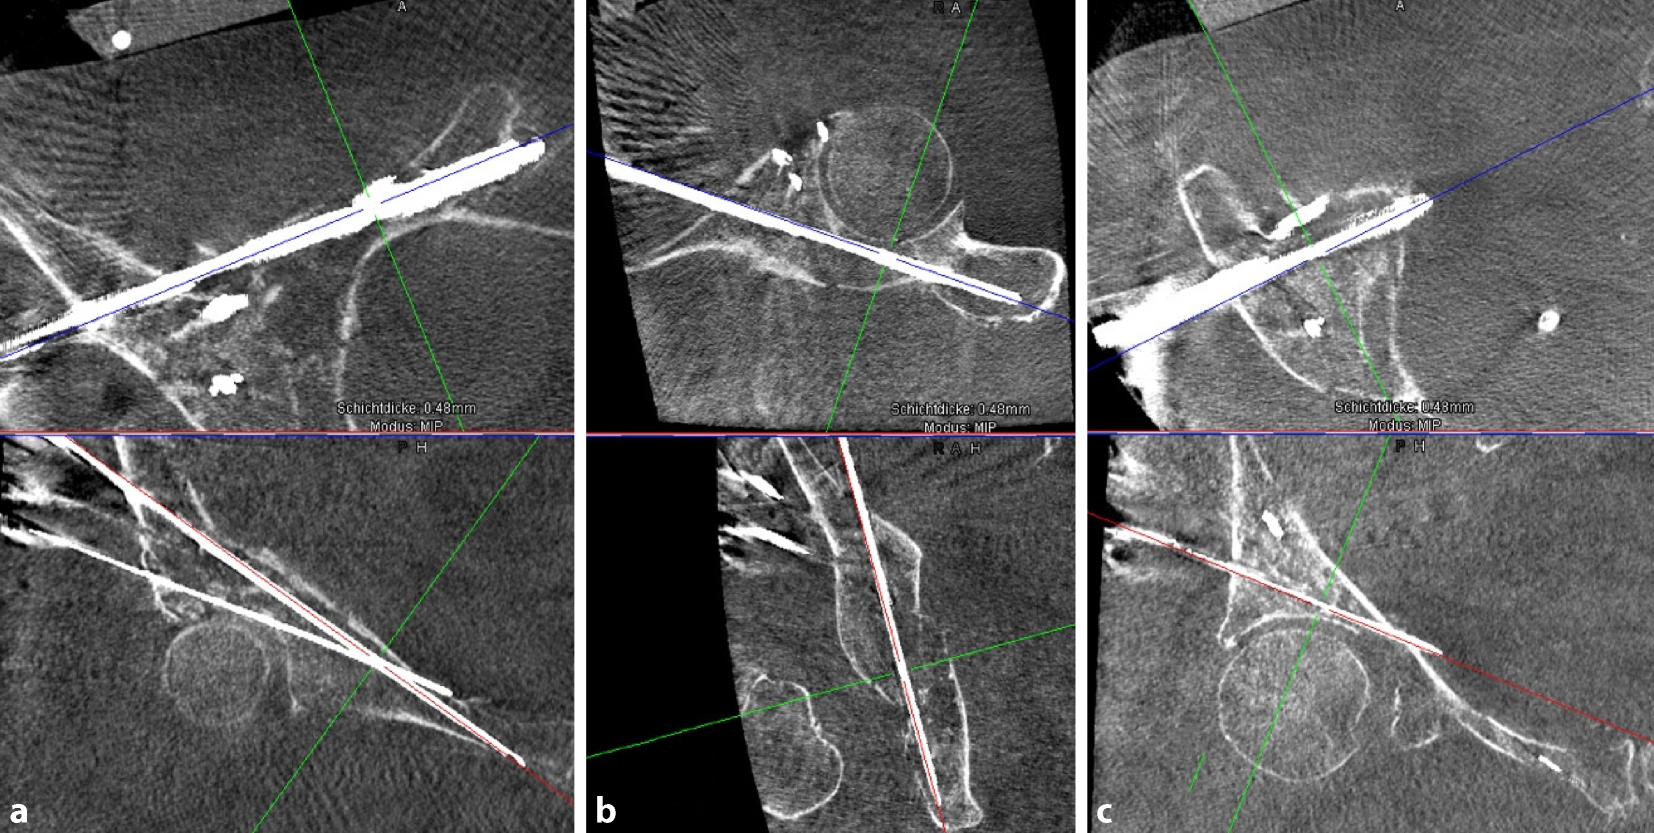

• Eine Computertomographie des Beckens zur genauen Darstellung der Frakturmorphologie und zur präoperativen Planung der Schraubenlage ist immer notwendig (Abb. 2).

Abb. 2

In der präoperativen CT-Diagnostik kann die genaue Frakturmorphologie festgestellt und mögliche Therapieoptionen können eruiert werden. In der Rekonstruktion stellt sich die leicht dislozierte T‑Fraktur des Azetabulums Typ 6 nach Letournel und Judet dar

Abb. 11

Nach navigierter Implantation der Drähte erfolgt eine erneute Kontrolle über den 3‑D-Scan, um mögliche Fehllagen auszuschließen und ggf. korrigieren zu können. Die Bildebenen können vom Operateur steril im OP eingestellt werden. Abgebildet zeigen sich die Führungsdrähte für die vordere Pfeilerschraube (a), für die hintere Pfeilerschraube (b) sowie für die supraazetabuläre Schraube (c) jeweils in 2 Ebenen (oben und unten)

Bild vergrößern